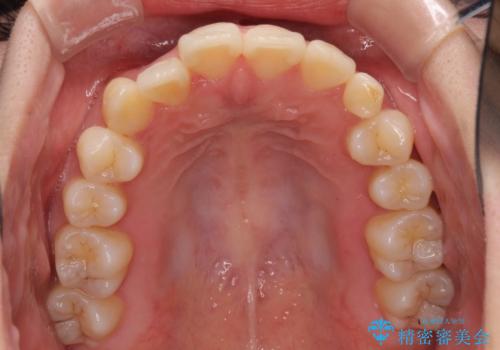

- 前歯のデコボコと残っている乳歯の部分へのインプラント治療を希望して来院された患者様です。

当初は目立たない上下裏側矯正を希望されていましたが、歯並びの悪さによる磨き残しが多く、歯肉炎が認められたため、より清潔な環境で治療を進められるインビザラインを選択することとしました。

また、インプラント治療については、インビザラインによる矯正治療中の最適なタイミングで治療を行い、治療期間の短縮を図ることとしました。

インプラントは、治療期間を短くすることが可能な、ストローマン社のSLActiveを使用することとしました。

前歯のデコボコが強かったため、上の奥歯を後方に動かす量が多くなり、結果として2年以上の治療期間を擁することとなりました。

インプラント治療は当初の狙い通り、矯正治療期間中に行い、スムーズに処置を進めることができました。

歯並びが整ったことで治療前に認められた歯肉炎は全くなくなり、患者様には大変満足していただきました。